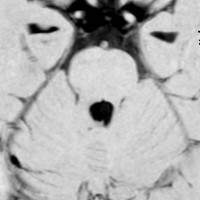

乳児期にてんかん発作で発症する内側側頭葉過誤腫

mesial temporal hamartomatous tumor

乳児期に全身性感帯痙攣発作で発症しました。左海馬鈎に強い石灰化があります。側頭葉硬化症とも言われるものです。この部位の過誤腫様の腫瘍は難治性てんかんとなることが多く,病変切除が必要となります。

脳波では前頭葉に蕀律動を認めます。切除は扁桃体と海馬鈎の摘出を目指すものです。